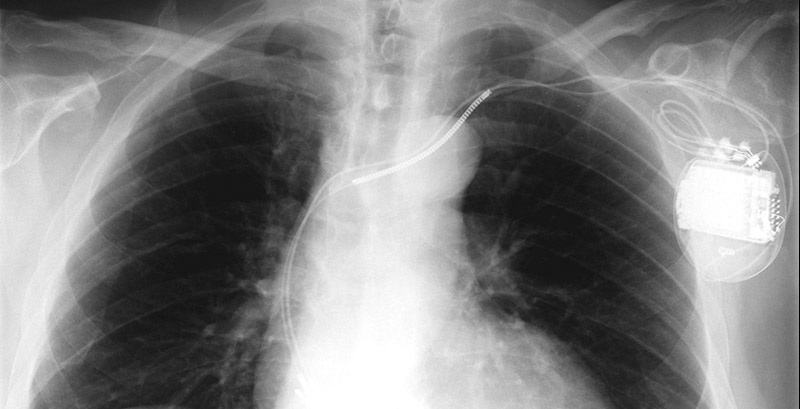

Herzschrittmacher

Verschiedene Störungen des elektrischen Systems des Herzens (Erregungsbildungs- und –leitungssystems) können dazu führen, dass das Herz vorübergehend oder dauerhaft zu langsam schlägt.

Dies kann zu verschiedenen Beschwerden wie Schwindel, Leistungsintoleranz und sogar Bewusstseinverlust (Synkope) führen. Solche zu langsamen Herzschläge können mit einem Herzschrittmacher korrigiert werden.